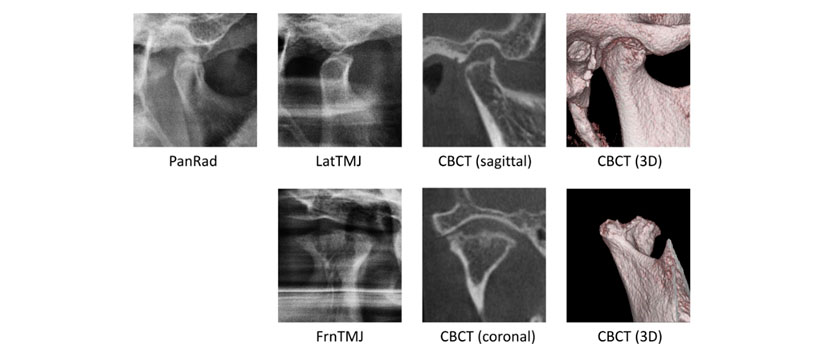

Otro tipo consiste en una combinación de proyecciones laterales frontales en la posición de mandíbula máxima abierta para cada ATM; este tipo de imagen es ventajoso porque la vista frontal puede proporcionar información adicional sobre los cambios en los huesos observados en la vista lateral (Fig. 1). Varios estudios han informado sobre la precisión diagnóstica de la proyección lateral de la radiografía de ATM panorámica con respecto a los cambios óseos de ATM con cráneos humanos secos, pero los estudios que emplean una proyección frontal con cráneos humanos son notorios. Además, poco se sabe acerca de la precisión diagnóstica de estas proyecciones en pacientes con osteoartritis de ATM.

Este estudio tuvo como objetivo evaluar la precisión diagnóstica y la confiabilidad de la radiografía  panorámica de la articulación  temporomandibular  para detectar lesiones óseas en pacientes con osteoartritis.  Para lo cual en este estudio incluyó 55 ATM de 44 sujetos a los que se les diagnosticó osteoartritis a ese nivel. Se sometieron a radiografía panorámica (PanRad), proyección lateral (LatTMJ) y frontal (FrnTMJ) y tomografía computarizada de haz cónico (CBCT). Todas las imágenes fueron examinadas por dos observadores en busca de aplanamiento, erosión y osteo-fitos en la cabeza condilar y la eminencia articular de la ATM. (Figura 1 y Figura 2).